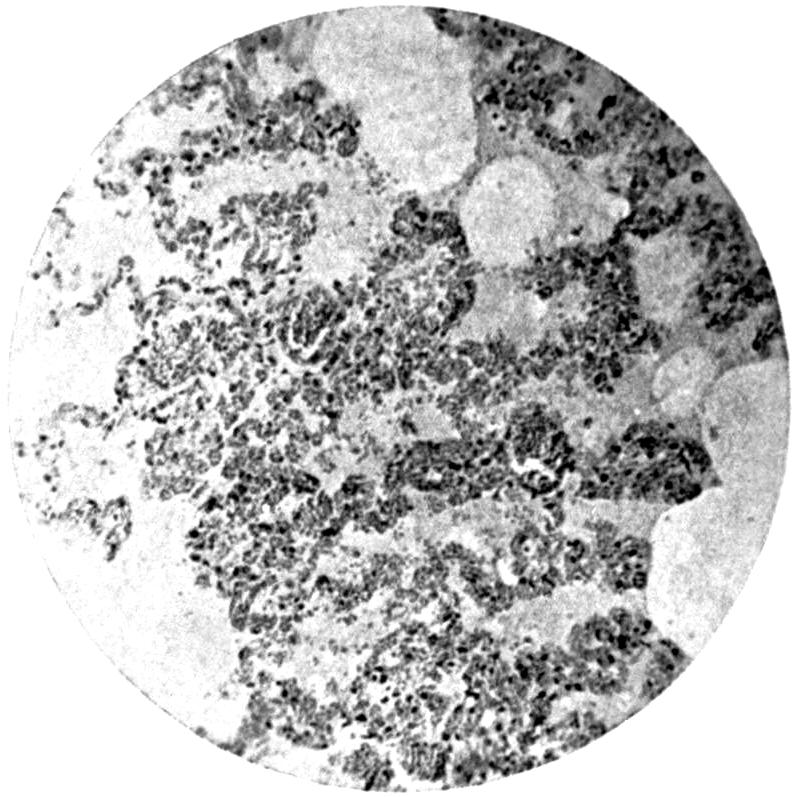

Plate I. 92

Plate II. 93

Plate III. 95